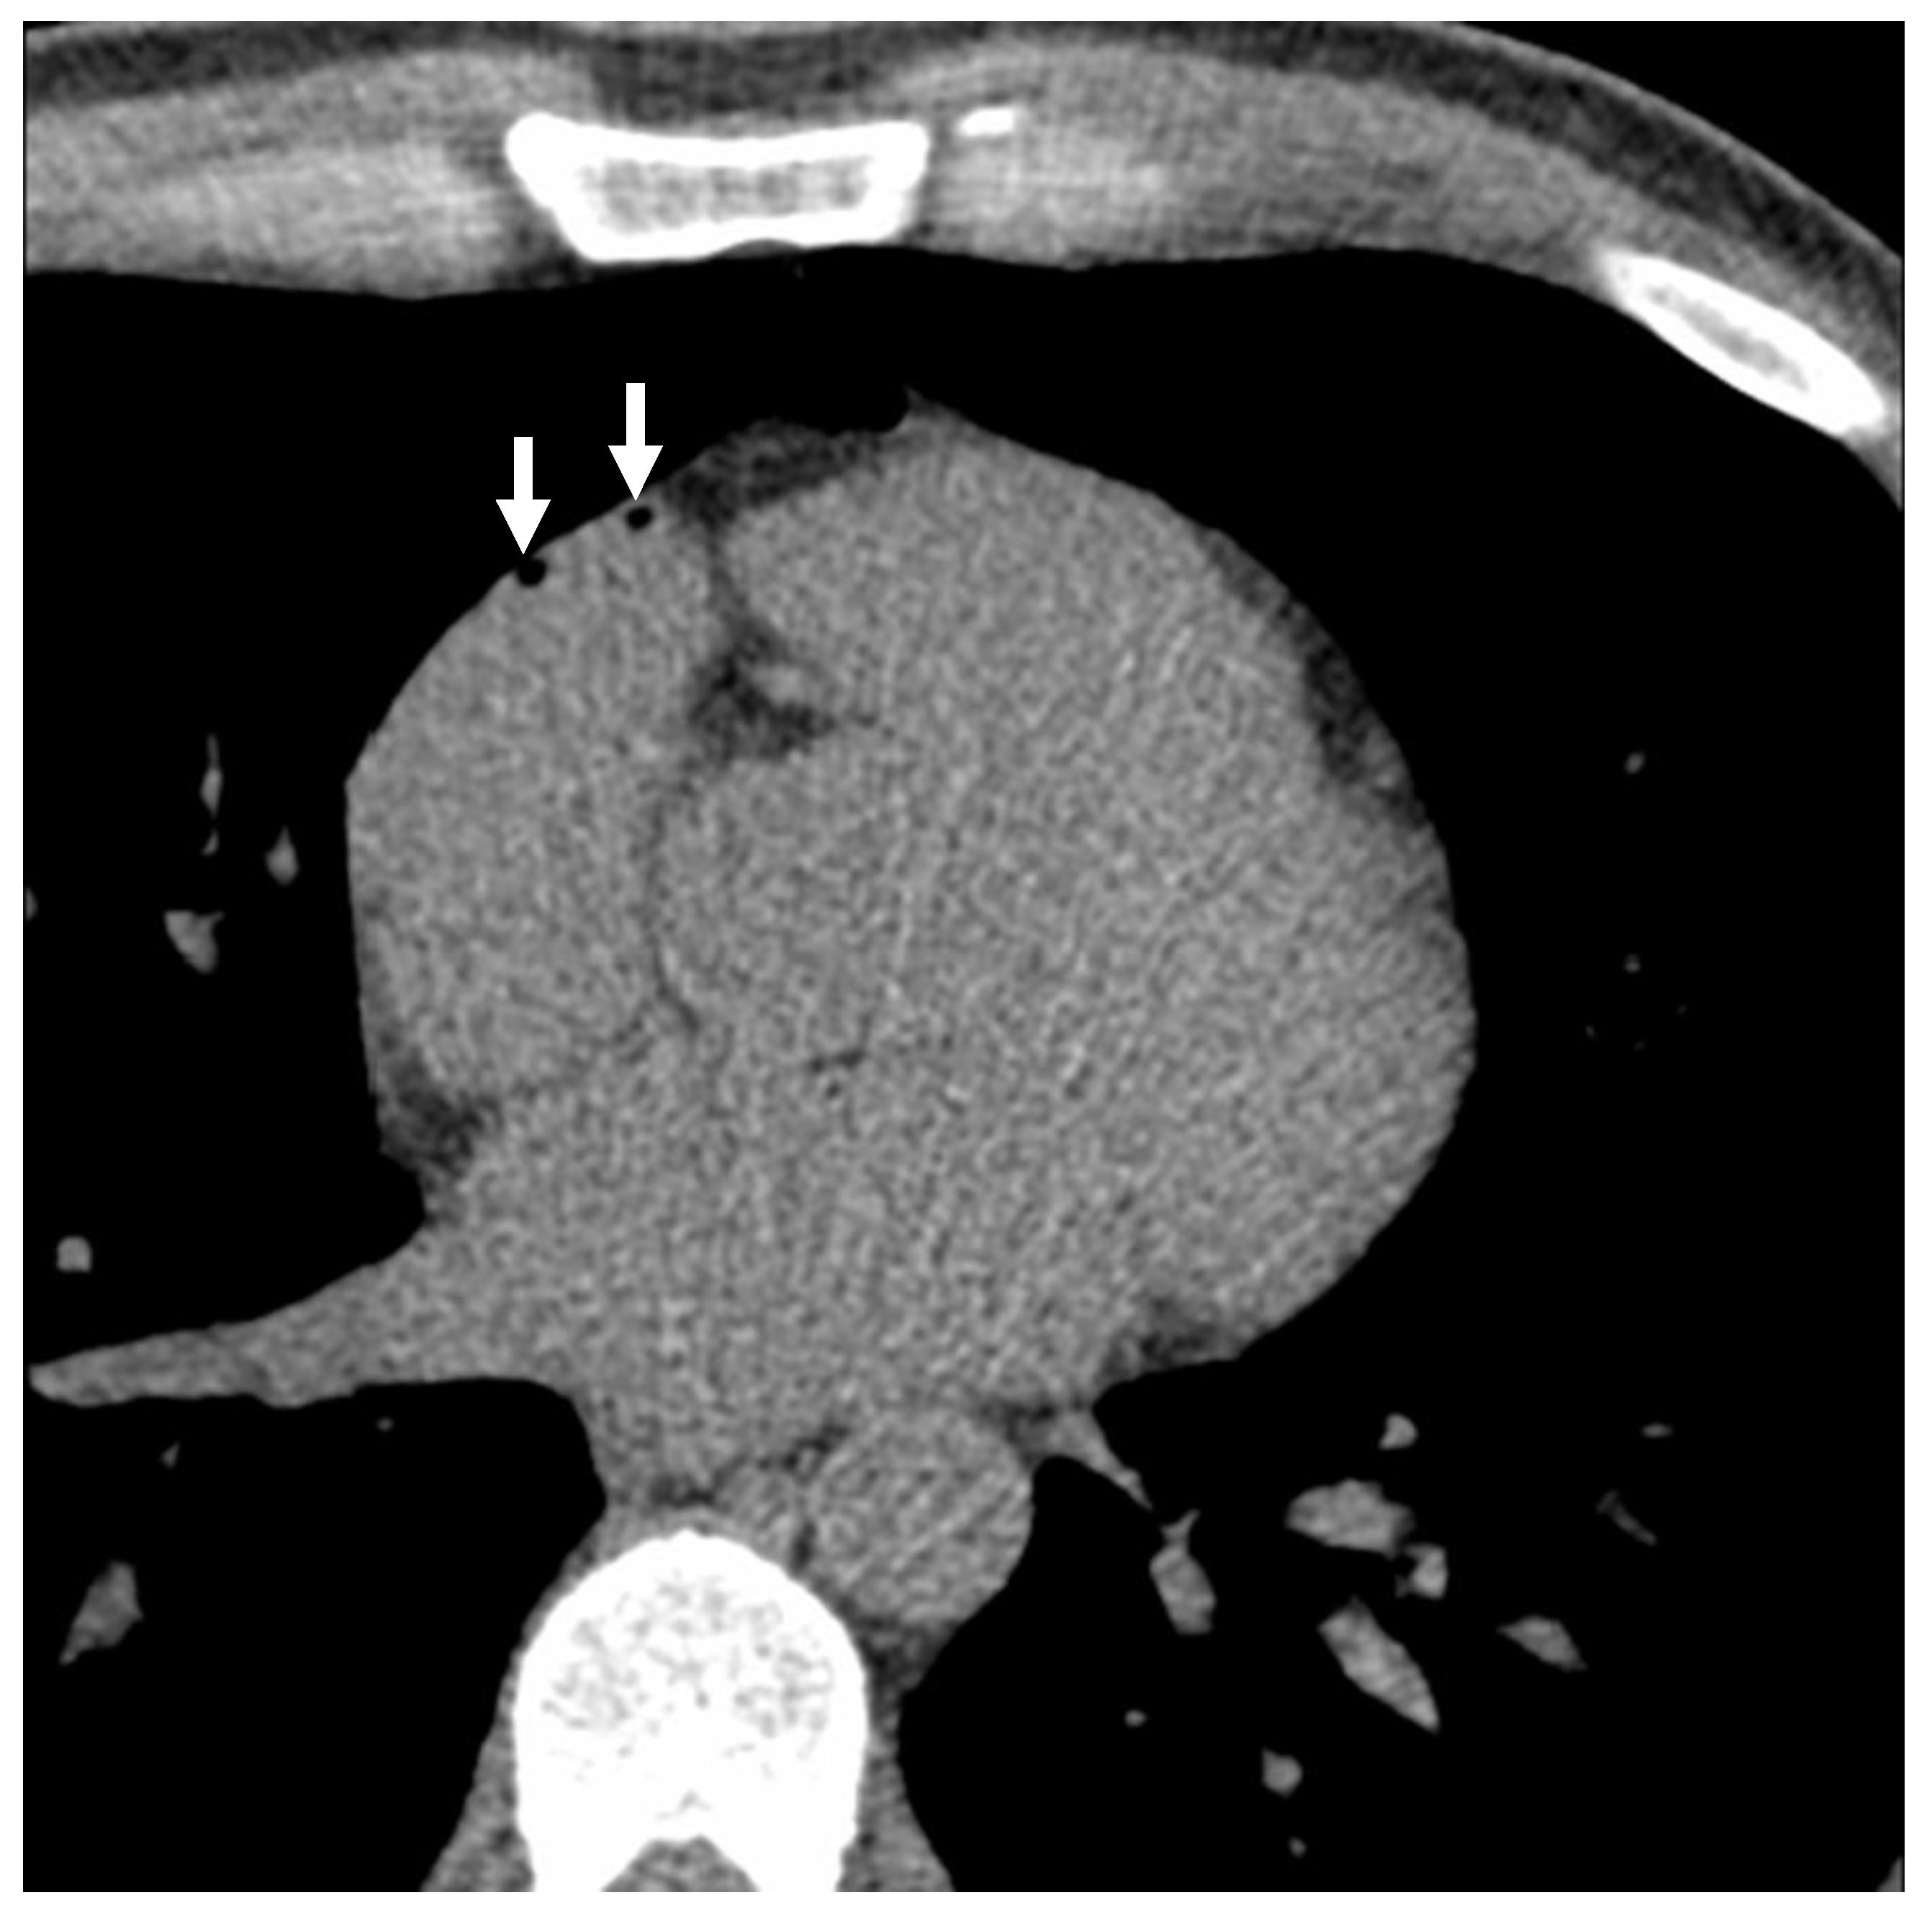

Figure 2. Cardiac computed tomography images with intravascular air in the right atrial appendage. Note: White arrows show the intravascular air volumes in a normal individual, prior to the administration of contrast, who underwent chest CT.

A total of 110 subjects underwent both NECCT and subsequent CECCT. 27 (24.5%) had intravascular air, with a subset of 8 (7.3%) showing air emboli in multiple locations on the NECCT portion of the examination, which was performed following intravenous cannulation. On the CECCT portion of the examination, 36 (32.7%) had evidence of intravascular air, with 9 (8.2%) showing air emboli in multiple locations (see Figure 1 and Figure 2). As demonstrated in Table 1, the average intravascular air volume among patients with emboli was 19.2 ± 25.4 µL and 14.8 ± 26.5 µL for the NECCT and CECCT studies, respectively.

Table 2 demonstrates the locations of intravascular air in the NECCT group. Air emboli were detected in the right atrial appendage (RAA), right internal mammary vein (RIMV), right ventricle (RV), right ventricle outflow tract (RVOT), and superior vena cava (SVC). The most common location for air volumes was the RAA/RA, with 21 (77.8%) out of 27 subjects demonstrating air emboli in RAA/RA. The highest average volume of air recorded per subject was found within the RIMV, at 35 ± 43.84 µL.

Table 3 demonstrates the locations of intravascular air in the CECCT group. Air volumes were found to be in similar locations to the NECCT group, but with a greater number of air emboli (45 subjects, in comparison to 35 subjects in the NECCT group). The greatest incidence of intravascular air was also found to be within the RAA, involving 27 patients (77.14%) and a total volume of 368 µL of intravascular air. The highest average volume of air attributed to a single patient was 35 ± 43.84 µL, found in the RIMV.